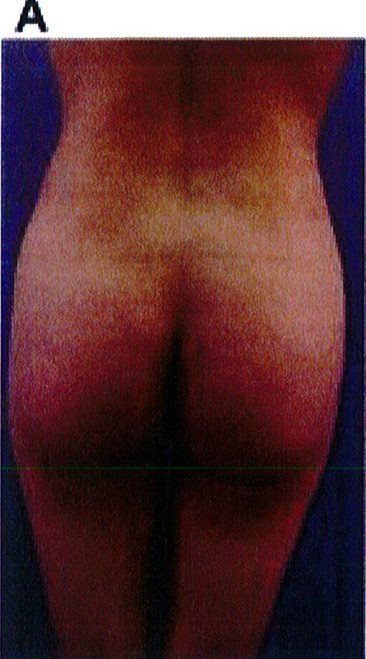

Hình. 18.. (A) Hình anh trước và (B) và sau phẫu thuật làm đầy mông của bệnh nhân được đặt khối implant dưới cân thể tích 225 mL, hai bên.

Bệnh nhân 31 tuổi tiền sử khỏe mạnh, có chỉ định nâng mông bằng implant do thiếu hụt thể tích. Hai khối anatomic implant 225 mL polyurethane dạng gel được đặt ở vị trí dưới cân. Sau phẫu thuật không ghi nhận biến chứng trong suốt quá trình hồi phục, vết mổ liền tốt (Hình 18).